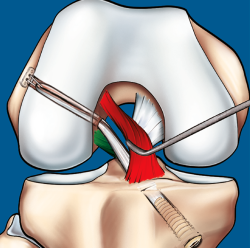

Figura 9. Esquema que ilustra el tratamiento con plastia de reconstrucción unifascicular posterolateral.

La reconstrucción selectiva del fascículo afectado sigue los principios básicos de la reconstrucción clásica anatómica del LCA (Figuras 9 y 10). Los autores realizan 3 portales: un portal anterolateral, lo más proximal posible con el fin de evitar la almohadilla grasa infrapatelar de Hoffa y tener una visión panorámica de toda la articulación; un portal AM alto y parapatelar, que utilizaremos como portal de visión y que nos va a permitir una mejor visualización de la huella anatómica femoral; y un portal AM accesorio, lateral al cóndilo femoral medial e inmediatamente superior al menisco interno, desde donde realizaremos el brocado del túnel femoral mediante técnica de manos libres(8). Otros autores recomiendan la realización del túnel femoral mediante técnica outside-in, considerando que ello facilita la realización del brocado femoral sin dañar las fibras del fascículo intacto(4).

Figura 10. Plastia de reconstrucción selectiva unifascicular (fascículo posterolateral –PL–). A: imagen artroscópica de la rodilla izquierda desde el portal anterolateral. Se evidencia una rotura completa crónica del fascículo PL con remanente tibial (flecha) e integridad del fascículo anteromedial (AM); B: imagen artroscópica de la rodilla izquierda desde el portal anterolateral. Colocación de la guía tibial tomando el remanente como referencia en una reconstrucción selectiva del fascículo PL; C: imagen artroscópica desde el portal AM que muestra la plastia de reconstrucción selectiva-aumentación del fascículo PL con autoinjerto de isquiotibiales (flecha).

Técnicamente, en la reconstrucción selectiva del fascículo AM o PM es fundamental reproducir la huella anatómica, tanto en el fémur como en la tibia. La mejor referencia para conseguir una posición correcta es localizar el remanente del fascículo roto(33).

Diferentes tipos de injerto pueden ser seleccionados, tanto autoinjerto como haloinjerto, según la preferencia de cada cirujano. Los autores utilizan preferentemente los tendones de la pata de ganso (autoinjerto), habitualmente de 7-8 mm de diámetro. Calibres superiores pueden llenar en exceso el espacio intercondíleo y comprometer tanto el fascículo preservado como la extensión de la rodilla. Los injertos con taco óseo también pueden ser utilizados, pero se desaconseja su uso por la mayor dificultad a la hora de pasar los mismos a través de los túneles y la mayor probabilidad de destruir el remanente ligamentoso(2,19).

En cuanto a los dispositivos de fijación del injerto, los autores utilizan un sistema de fijación suspensoria ajustable en el fémur y un tornillo interferencial en la tibia, normalmente 1 mm superior al calibre del túnel brocado. Para la reconstrucción selectiva del fascículo PL, fijamos el mismo a 0° para minimizar el riesgo de rerrotura y, para el fascículo AM, lo fijamos a unos 20°, en ambos casos pretensionado y sumergido en una solución antibiótica con vancomicina para minimizar el riesgo de infección(34).